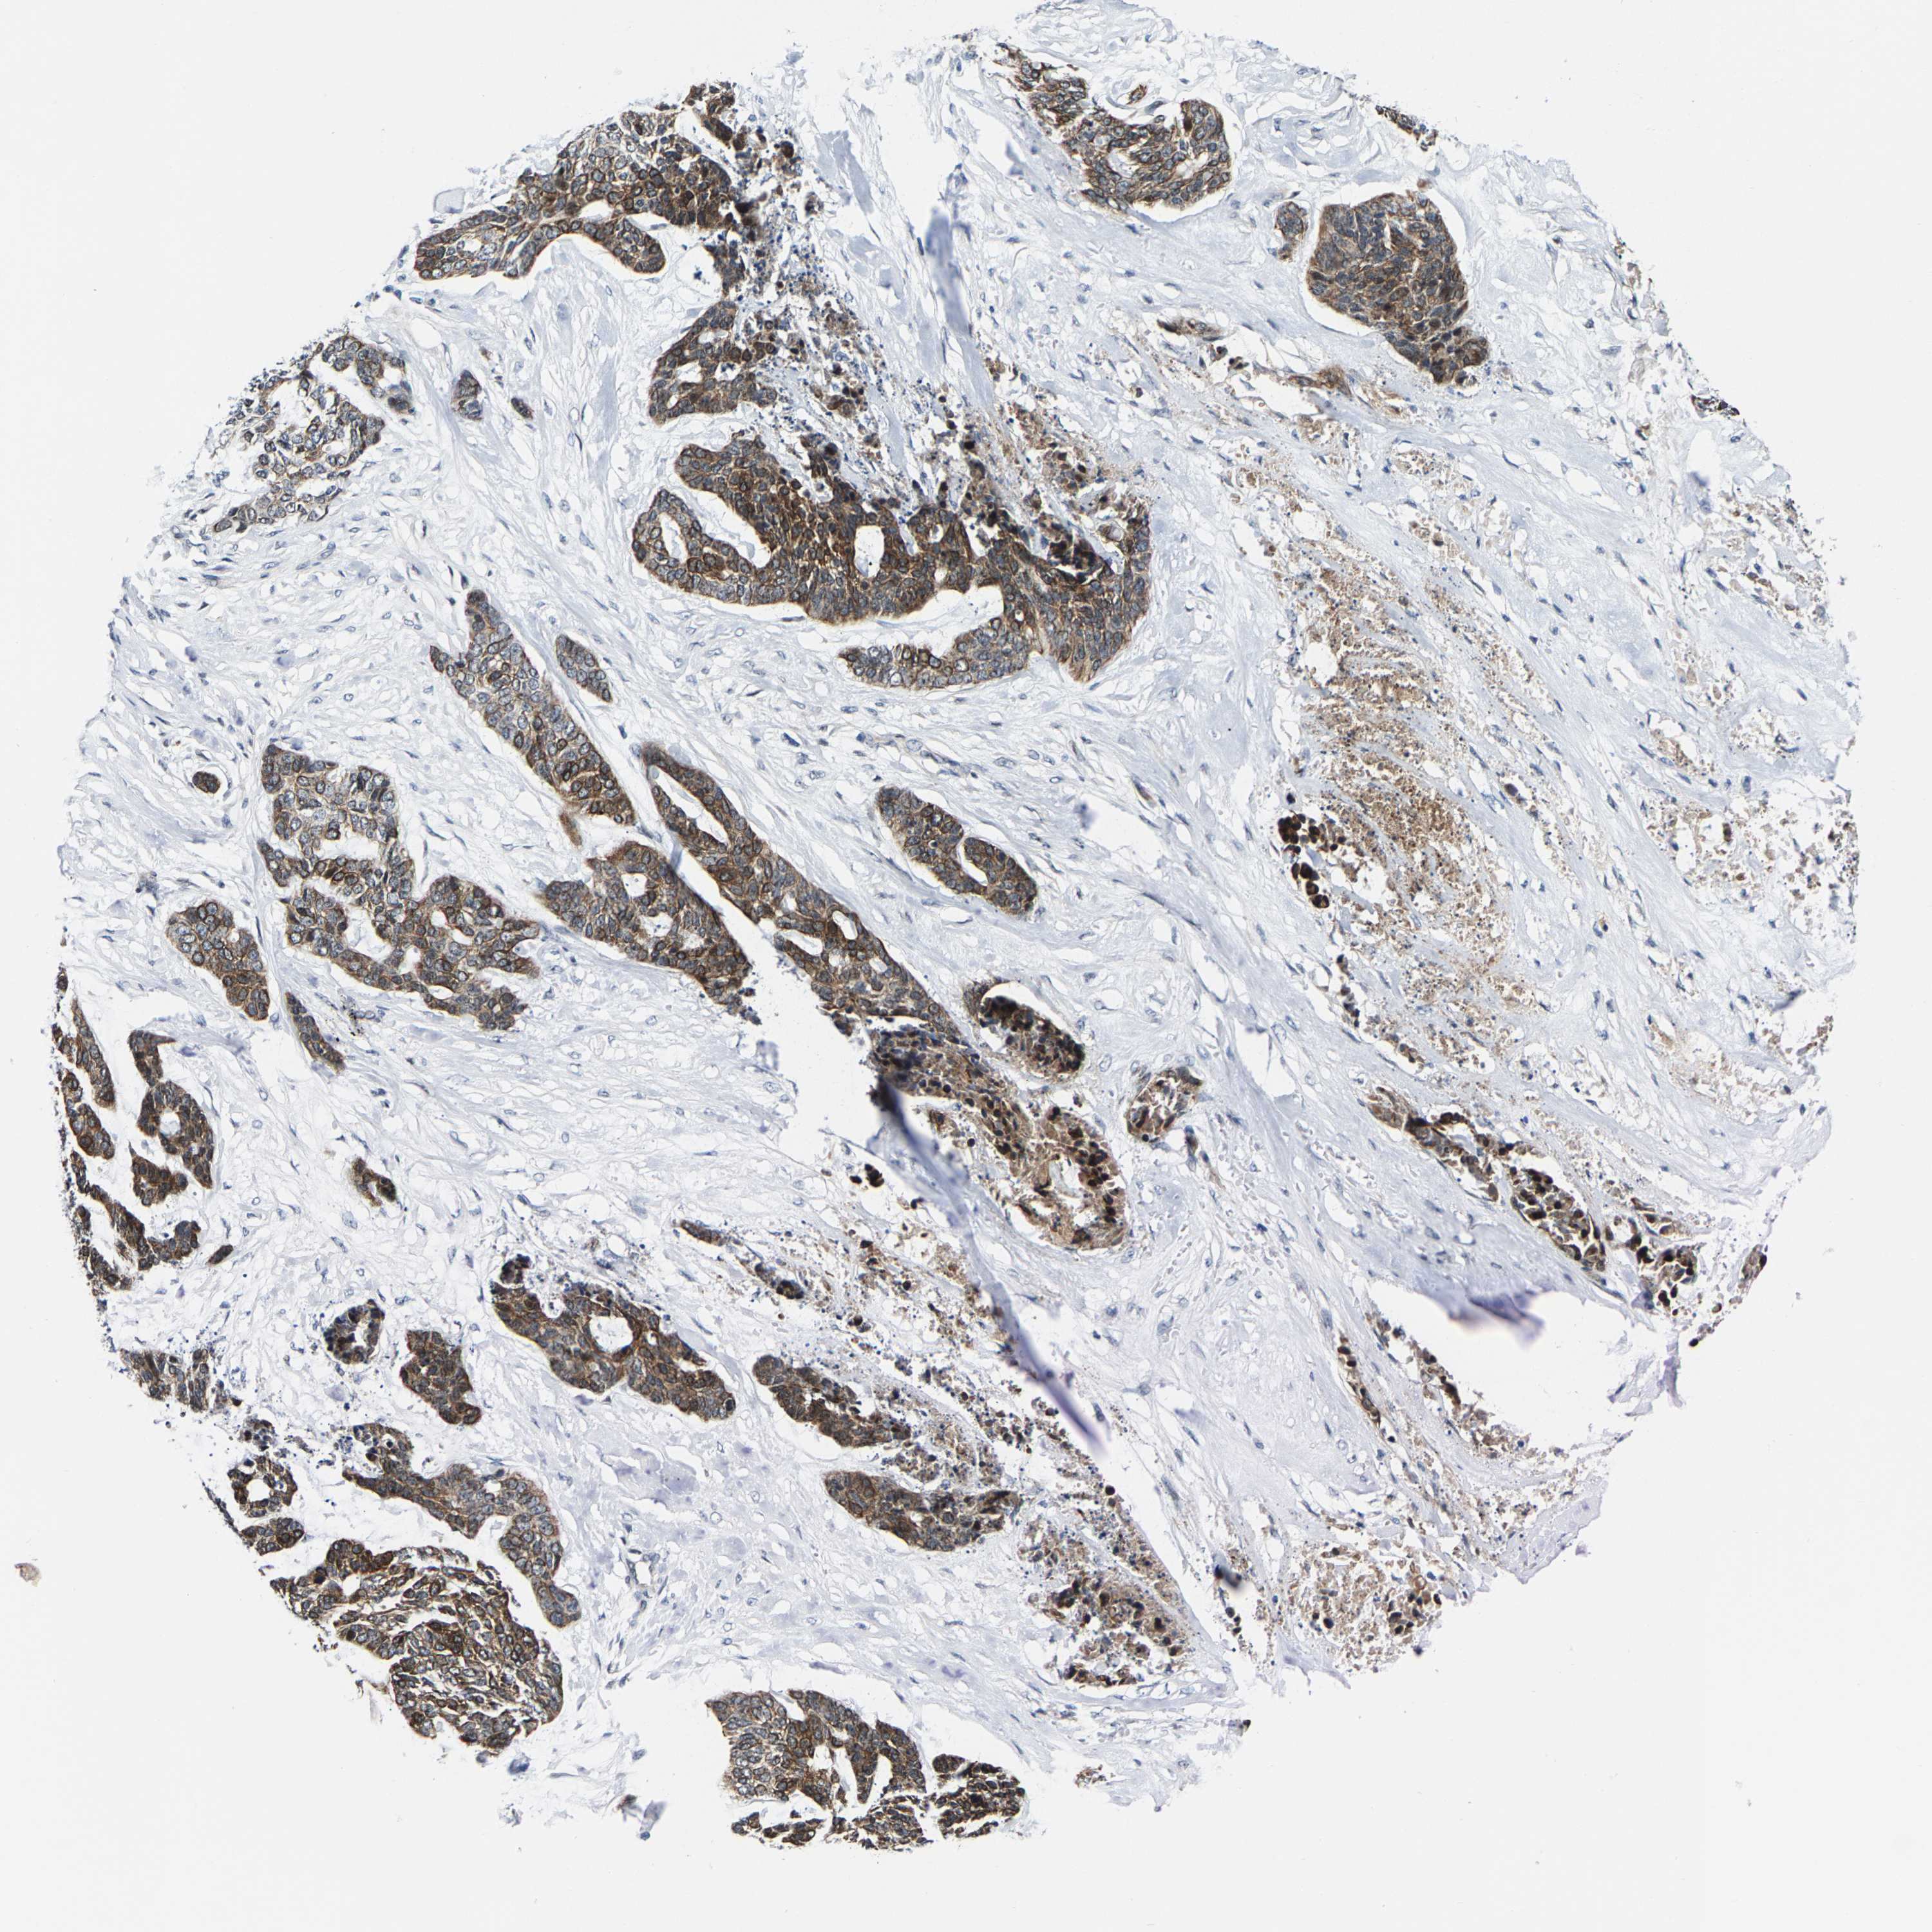

SKIN CANCER - Protein expressioni

A mouse-over function shows sample information and annotation data. Click on an image to view it in a full screen mode. Samples can be filtered based on level of antibody staining by selecting one or several of the following categories: high, medium, low and not detected. The assay and annotation is described here.

Antibody stainingi

Antibody staining in the annotated cell types in the current human tissue is reported as not detected, low, medium, or high, based on conventional immunohistochemistry profiling in selected tissues. This score is based on the combination of the staining intensity and fraction of stained cells.

Each image is clickable and will lead to virtual microscopy that enables deeper exploration of all samples and also displays staining intensity scores, fraction scores and subcellular localization as well as patient and tissue information for each sample.

Antibody HPA021076

Staining

High

Medium

Low

Not detected

Intensity

Strong

Moderate

Weak

Negative

Quantity

>75%

75%-25%

<25%

None

Location

Nuclear

Cytoplasmic/membranous

Cytoplasmic/membranous,nuclear

Basal cell carcinoma

Squamous cell carcinoma, NOS

Squamous cell carcinoma, metastatic, NOS